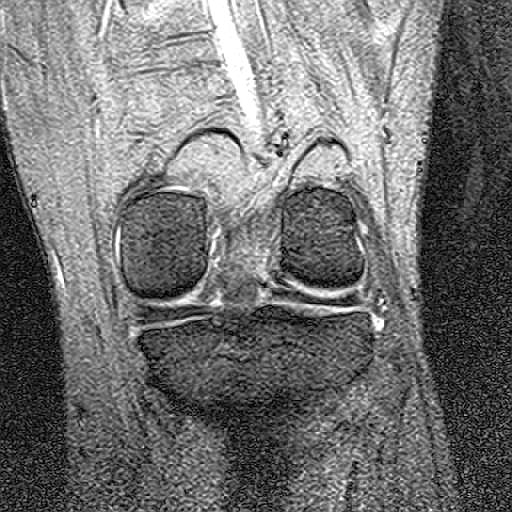

昨日は病院にMRIを撮りにいったんだった。

で、画像をCD-Rに焼かれたのを頂いて帰ったわけです。

まぁ、こんな感じ。

まぁ、医者じゃねーから分からんけど。

あ、俺のひざには愉快な奴が居るわ。

00000015.jpg